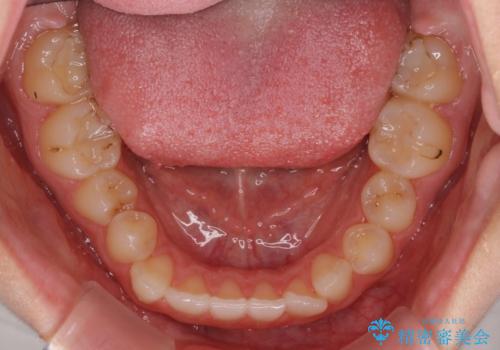

- 前歯のデコボコと八重歯を気にして来院された患者様です。

目立たない装置を希望されたので、上顎が裏側装置のハーフリンガルを選択し、左右上顎小臼歯1本ずつを抜歯して、矯正治療を行うこととしました。

治療期間の目安は2年半~3年間でしたが、予定通り治療が進み、2年半弱で終えることができました。

歯列はきれいに整い、治療期間も予定通りであり、患者様には大変満足していただきました。